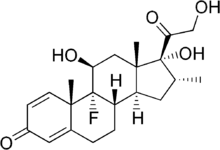

Corticoïde

Un traitement adjuvant par corticoïdes (habituellement la dexaméthasone) a plusieurs bénéfices démontrés tels que la diminution du risque de surdité[51] et un meilleur pronostic neurologique à court terme[52] chez les adolescents et les adultes dans des pays à revenus élevés et à prévalence du VIH faible[53]. Certaines études sont en faveur d'un effet sur la réduction de la mortalité[53] tandis que d'autres ne retrouvent pas une telle association[52]. Les corticoïdes apparaissent également bénéfiques dans la méningite tuberculeuse chez les sujets non infectés par le VIH[54].

Il est recommandé de commencer la corticothérapie juste avant l'antibiothérapie et de la poursuivre pour 4 jours[26],[28],[55]. Étant donné que l'efficacité de ce traitement est essentiellement réservée aux cas de méningite pneumococcique, certaines recommandations préconisent de l'arrêter lorsqu'un autre germe que le pneumocoque est identifié[10],[26]. Le mécanisme d'action supposé est la suppression d'une hyperactivité inflammatoire[56].

Chez l'enfant, l'utilité de la corticothérapie dans les pays à faibles revenus n'est pas confirmée, contrairement à ceux des pays à hauts revenus, sans que les raisons soient évidentes[52]. Dans les pays à hauts revenus, l'utilité des corticoïdes est plus importante en cas de méningite à Haemophilus influenzae[10],[57]. La corticothérapie est donc recommandée lorsque H. influenzae est en cause, et reste controversée dans les autres cas[10].